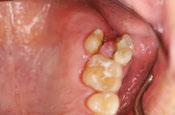

A 64-year-old male presented to the dental clinic for extraction of non-restorable maxillary left first, second, and third

12 Implant Practice US Volume 16 Number 1 TECHNIQUE

Figure 1: The patient’s panoramic radiograph upon initial consultation

molars in January 2019. The past medical history was significant for cystic fibrosis and depression. He had an allergy to sulfa medications and was taking the following medications: Pulmozyme® (dornase alpha), testosterone, prednisone, and nifedipine. The patient presented with a chief complaint of “I didn’t think I was going to live this long with cystic fibrosis, but I did, and now I am ready to take care of my needs.” The clinical examination was significant for a grossly carious dentition in need of repair (Figure 1). After reviewing several options, it was decided to extract the non-restorable left maxillary first, second, and third molars and to restore the maxillary left first and second molars with fixed implant-retained restorations. With potential healing concerns secondary to his cystic fibrosis, the addition of platelet-rich fibrin (PRF) was discussed. The patient was taken to the surgical operatory where the blood pressure was taken, a pulse oximeter placed, and an IV was started using a 21-gauge butterfly catheter in the right antecubital fossa. PRF protocol was followed using Intraspin® centrifuge (BioHorizons; Birmingham, Alabama), and anesthesia was maintained thereafter using a balance technique. Maxillary left first, second, and third molars were surgically removed, and the resulting extraction sockets were curetted free of granulation tissue. PRF clots and membranes were prepared as described by Choukroun, et al.15 The PRF was mixed 50/50 with MinerOss® mineralized allograft cancellous bone particles (BioHorizons; Birmingham, Alabama) resulting in a “sticky bone preparation” that was placed in the maxillary left first and second molar sockets (Figure 2). Two PRF membranes were placed across the extraction sites (Figure 3), and 3-0 PTFE interrupted sutures were placed affording good wound apposition (Figure 4). Adequate soft tissue healing was observed at a 3-week postoperative check.